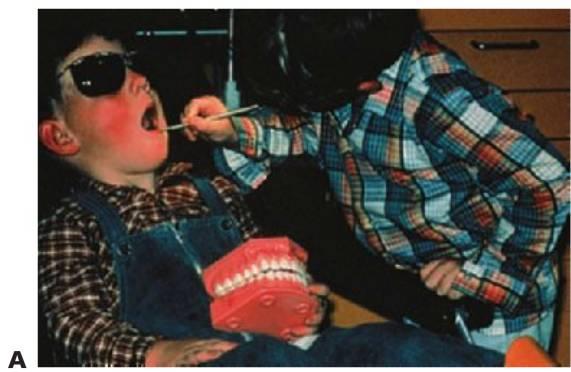

- Comunicación al nivel adecuado para el niño (fig. 2.1).

Objetos y situaciones de estimulación y distracción (fig. 2.2)

- Se debe familiarizar a los niños con instrumentos adecuados.

- Desarrolle la conversación inicial en una sala habilitada al efecto. La atención ha de centrarse en instruir al niño, fomentar su comodidad y hacer que la visita sea una experiencia positiva y divertida para él. Son preferibles las técnicas más simples y menos invasivas. Suele ser útil presentarle al niño la sala y al personal, haciendo alusión a los pósteres y elementos decorativos.